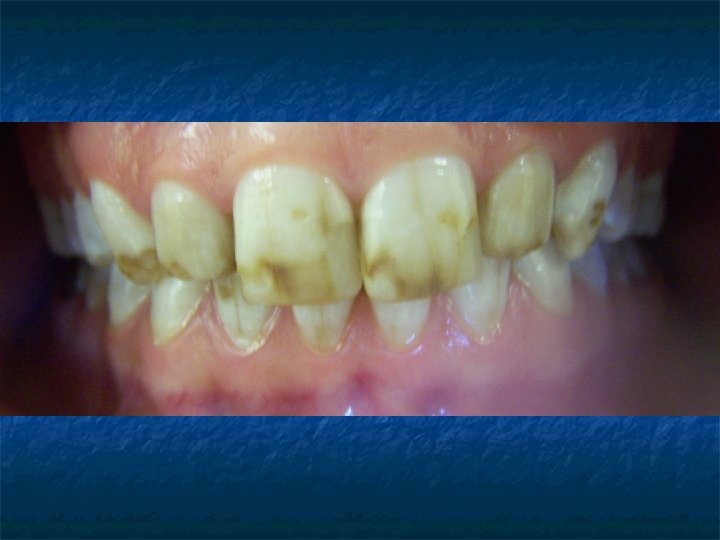

Adli Dişhekiminin Kimlik Tespitinde Yararlandığı Özellikler: n n n n n Dişler, Dental kayıtlar, Radyografiler, Dental fotoğraflar, Dental modeller, Diş ve damak ve ısırık izleri, Vücut izleri, Restorasyon ve protezler, Tükürük.

n Dişlerden sosyokültürel farklılık, alışkanlık ve mesleklerin belirlenmesi

n Restorasyon ve protezlerin incelenmesi